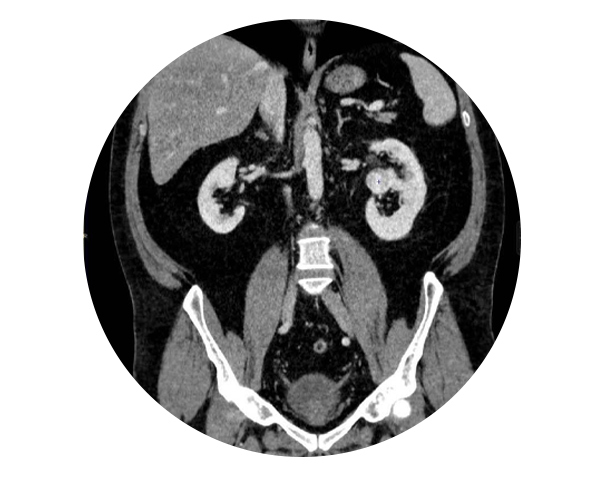

Practicăm urologia modernă care folosește tehnici și proceduri medicale avansate pentru diagnosticarea și tratamentul afecțiunilor urologice, proceduri care sunt actualizate continuu.

Urologia modernă se bazează pe tehnici avansate și inovatoare pentru a oferi tratamente eficiente și personalizate.